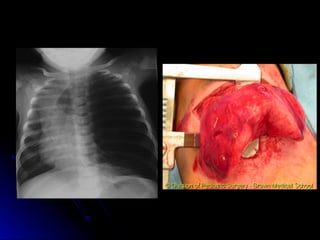

Congenital Diaphragmatic Hernia

(CDH)

 Most commonly on left side

Most commonly on left side

 Incidence 1:2000 to 1:5000

Incidence 1:2000 to 1:5000

 Often associated with other malformations

Often associated with other malformations

 Frequently diagnosed prenatally

Frequently diagnosed prenatally

 Avoid bag-mask PPV

Pre-op CDH

 Delayed surgical repair – usually after 72

Delayed surgical repair – usually after 72

hrs of age

Post-Op CDH

 Survival continues to be around 40-50%.

Survival continues to be around 40-50%.